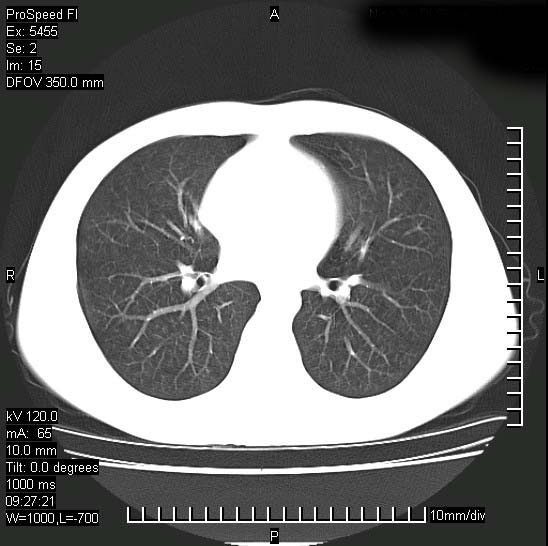

以下是引用zjzjr在2008-12-3 20:50:00的发言:[br]考虑泛细支气管肺炎,建议进一步检查除外肺出血性疾病如含铁血黄素沉着症、肺肾综合征等。

以下是引用zjzjr在2008-12-3 20:50:00的发言:[br]考虑泛细支气管肺炎,建议进一步检查除外肺出血性疾病如含铁血黄素沉着症、肺肾综合征等。

以下是引用光线在2008-12-3 20:19:00的发言:[br]双肺间质性改变。